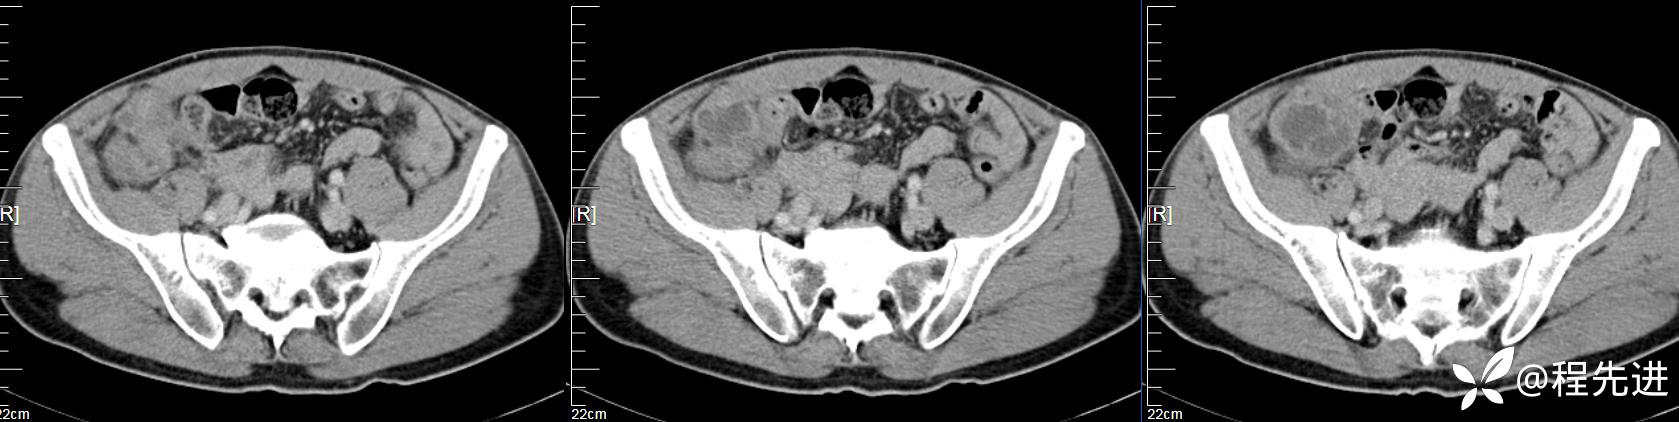

【患者信息】:男,61岁

【现病史及既往史】:右下腹部疼痛伴腹胀2天

【影像检查】